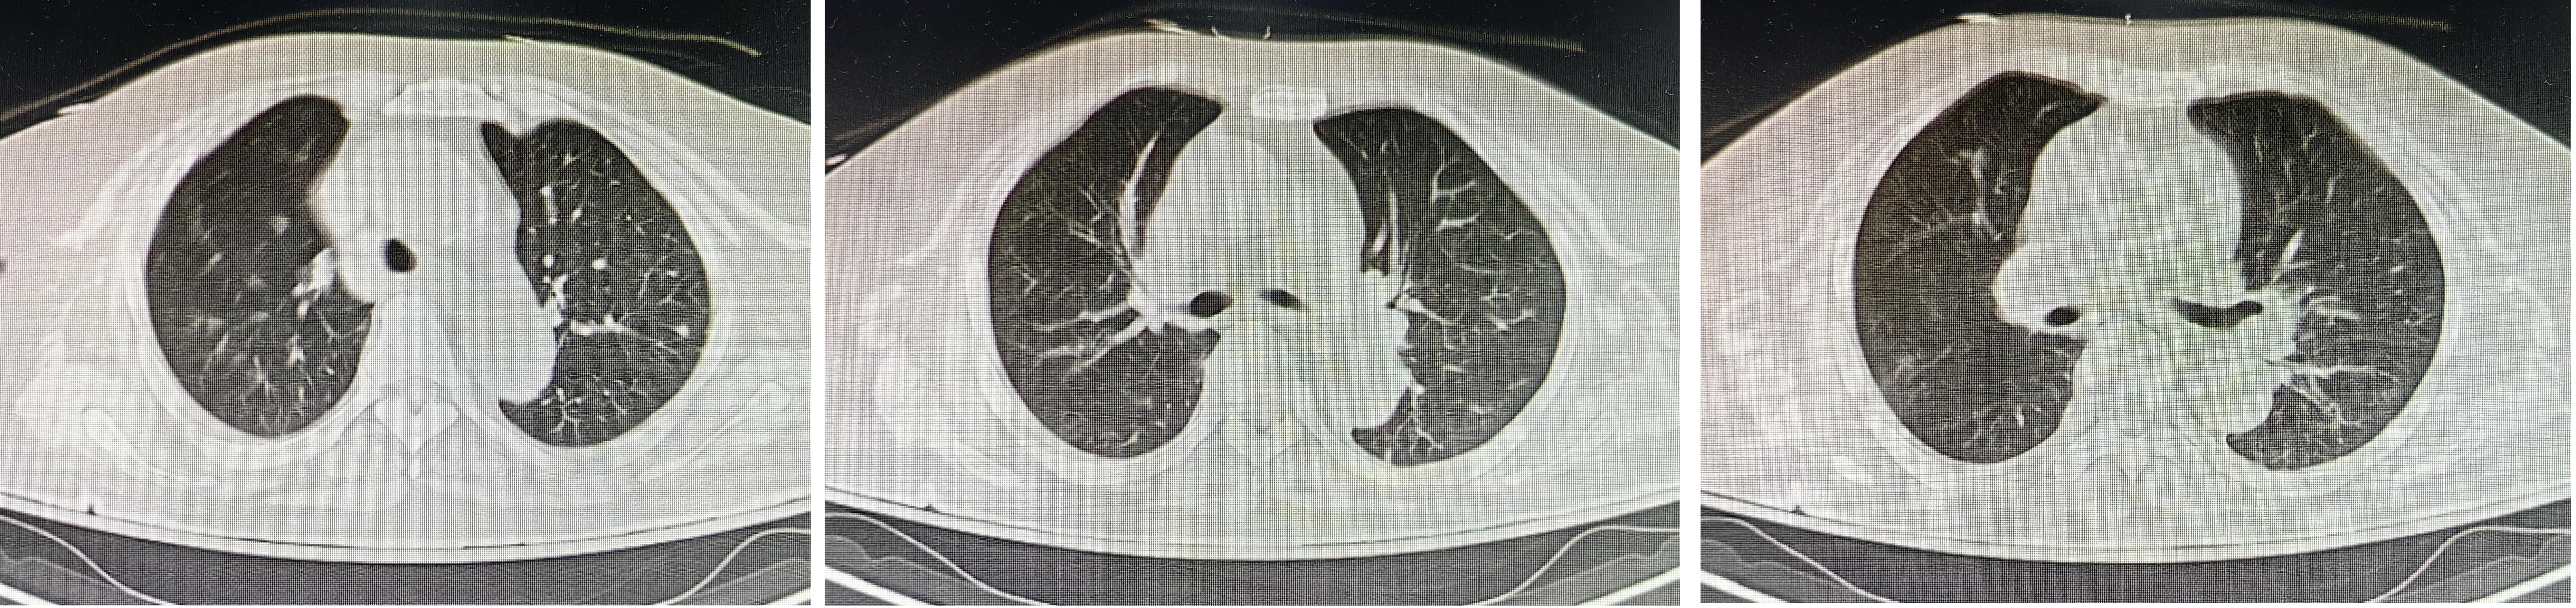

入院辅助检查:急诊血常规:“白细胞计数: 87.5×109/L,中性粒细胞计数: 27.6×109/L,占比31.5%,血小板计数: 673×109/L,淋巴细胞计数:55.8×109/L,占比63.8%,嗜酸性细胞计数: 0.00×109/L,单核细胞计数:3.9×109/L,超敏C反应蛋白:97.0 mg/L”。血气分析:“pH: 7.4,PaO2: 48 mmHg,PaCO2: 30.5 mmHg,SatO2: 83%,BE: -5 mmol/L,乳酸:2.5 mmol/L”。急诊生化常规:“血钠133 mmol/L,肌酐207 μmol/L”。胸部CT平扫(见图 1):“①两肺支气管扩张伴少许感染灶;②两肺散在实性结节;③纵隔、两肺门及腋下多发淋巴结”。头颅CT未见明显异常。

| 图 1 抢救室行胸部CT示气管及左右主支气管内未见异物 |